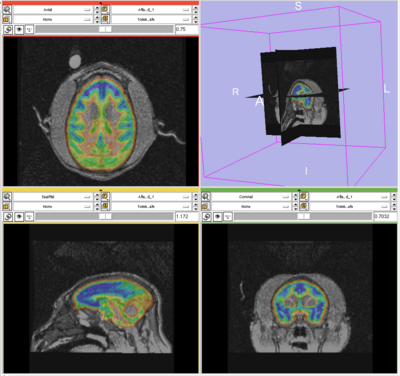

Segmentation Results

1. The results for the best and worst segmentations are shown in the following. For each subject, the first figure shows the alignment of Gray matter atlas (these will be changed to checker board figures aligning target and the whole brain atlas soon) with the brains, and the second figure shows the segmentation results.

Worst Segmentation: Tommy